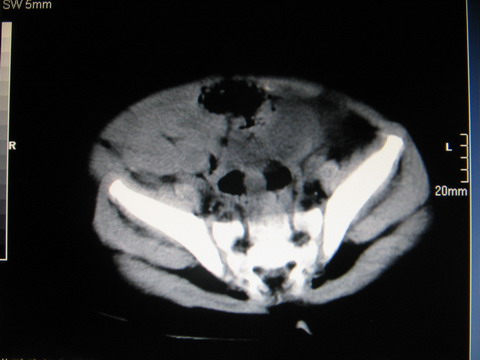

标题: PED0552:男1岁,双肾区CT

胎龄5个月时b超示左肾积水,现一岁后复查

左肾重度积水!

左肾重度积水!考虑肾盂输尿管交界处先天性狭窄或闭塞所导致

左肾重度积水.

左肾重度积水。

左肾重度积水(先天性左输尿管狭窄所致?)。

先天性左输尿管狭窄所致左肾重度积水。